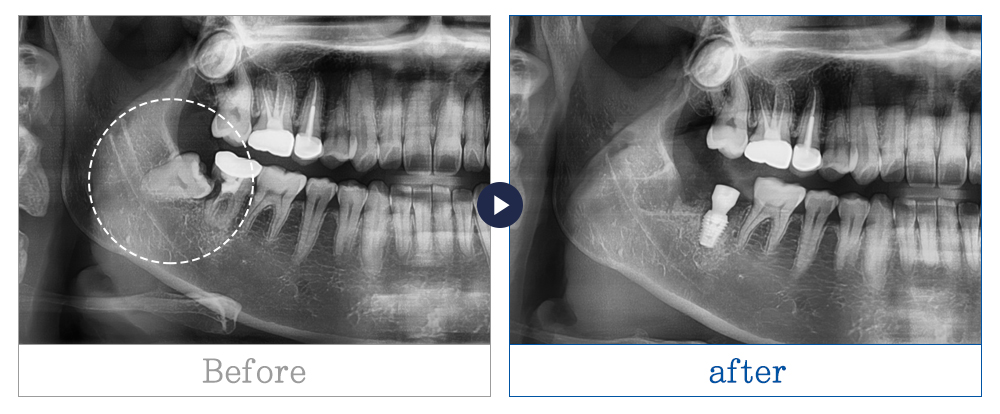

제목 사랑니 발치 사례 카테고리 사랑니발치

사랑니 발치 사례

치료기간 3개월 이상

* 환자의 상황, 상태, 치료 계획마다 치료 기간은 상이할 수 있습니다